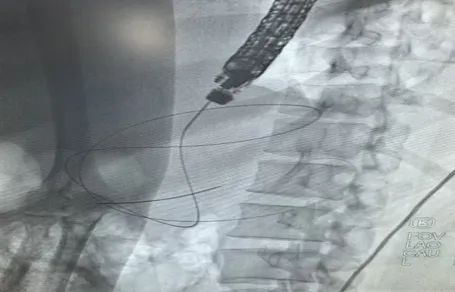

谭琰主任EUS引导穿刺-置入导丝

这根支架在囊肿和胃腔之间搭起一座“桥梁”,将胰腺假性囊肿囊液及坏死物质引流至消化道,随之排出体外。整个过程严格遵循“EUS引导穿刺-置入导丝-针状刀切开-扩张窦道-置入双猪尾塑料支架”的标准化流程,精准建立引流通道。整个手术无需在体表制造任何切口,实现了真正的“超级微创”。